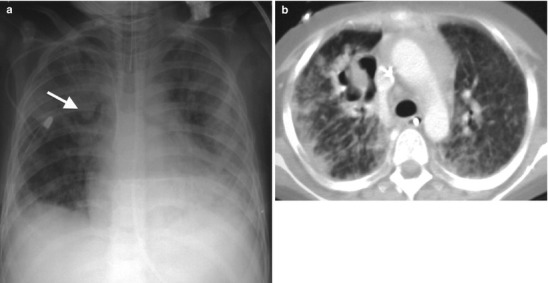

Fig. 13.19.

Progression of Ghon focus. CT scan images from two different patients showing advanced progression of lung parenchymal disease from dense consolidation with ischemic changes (a) and cavitary necrosis with cyst formation (b)